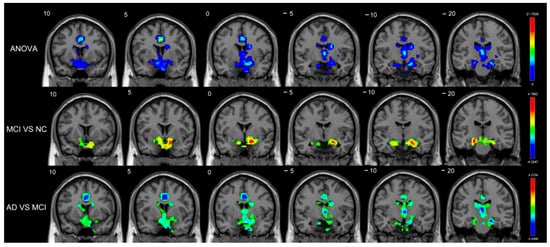

| MCI vs. NC | |||||

| Long-range | Amygdala_R | BA34 | (21,−2,−17) | 4.4157 | 38 |

| Amygdala_L | - | (−13,2,−15) | 3.3582 | 6 | |

| Putamen_L | BA25 | (−14,7,−9) | 3.2804 | 7 | |

| Pallidum_R | BA25 | (12,3,−5) | 3.1270 | 5 | |

| AD vs. NC | |||||

| Short-range | Caudate_L | - | (−7,1,11) | −2.9712 | 29 |

| Caudate_R | - | (9,5,7) | −2.8622 | 8 | |

| AD vs. MCI | |||||

| Short-range | Caudate_L | - | (−18,−21,23) | −3.2570 | 9 |

| Caudate_R | - | (16,−18,21) | −2.8545 | 4 | |

| Long-range | Caudate_L | - | (−15,14,18) | −3.7649 | 66 |

| Caudate_R | - | (17,6,23) | −3.7601 | 54 | |

| Amygdala_R | BA48 | (19,2,−11) | −3.6551 | 20 | |

| Pallidum_R | BA48 | (19,−3,−2) | −3.4747 | 9 |